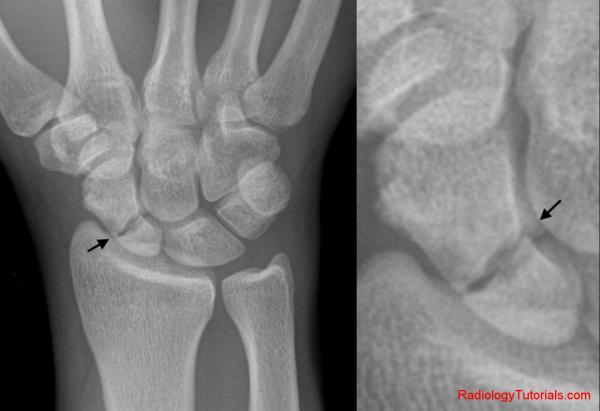

skafoid kırığı

Günlük hayatımızda ya da spor aktiviteleri sırasında düşme, sert top gelmesi gibi durumlar el bileğinde ağrı, şişlik ve hareket kısıtlılığı oluşturabilir. İlk bakışta hasta tarafından önemsenmeye...